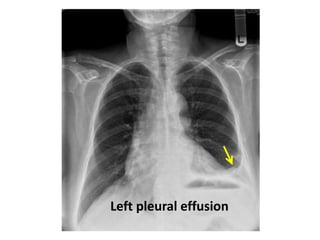

Left pleural effusion

Emphysema